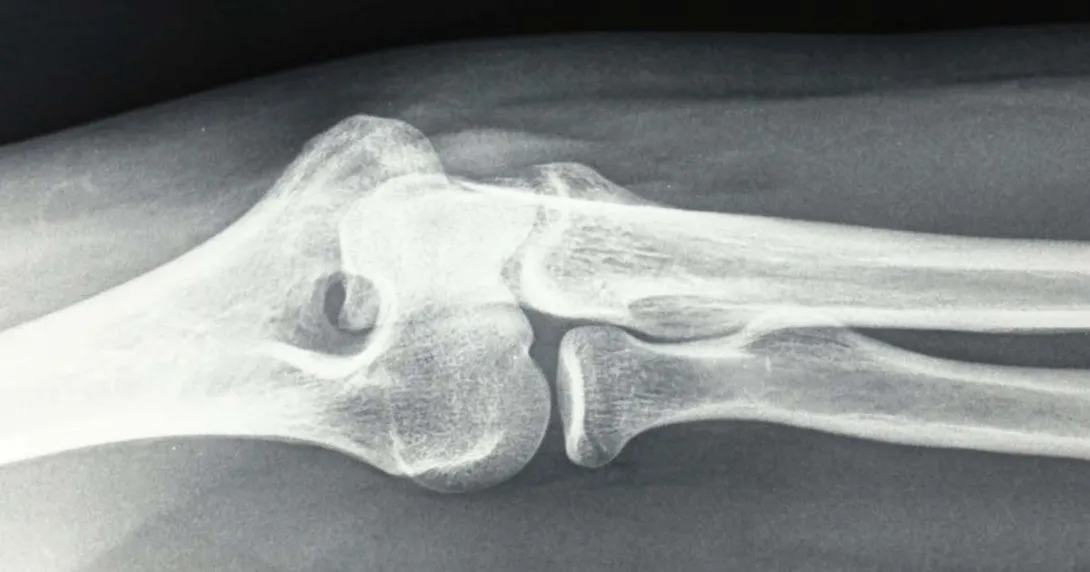

The Atlanta-based company offers an FDA 510(k)-cleared handheld X-ray system that can be used for static and serial diagnostic images of the extremities, dubbed the Micro C Medical Imaging System. The device connects directly to OXOS' cloud platform, where physicians can access images.